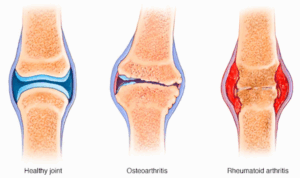

Arthritis

Arthritis is the swelling and tenderness of one or more joints. The main symptoms of arthritis are joint pain and stiffness, which typically worsen with age. The most common types of arthritis are osteoarthritis and rheumatoid arthritis.